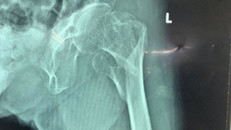

Nối các mảnh xương gãy cho cụ bà 101 tuổi

BV Chấn thương-Chỉnh hình TP.HCM vừa nối lại thành công các mảnh xương gãy cho cụ bà 101 tuổi bị té ngã.